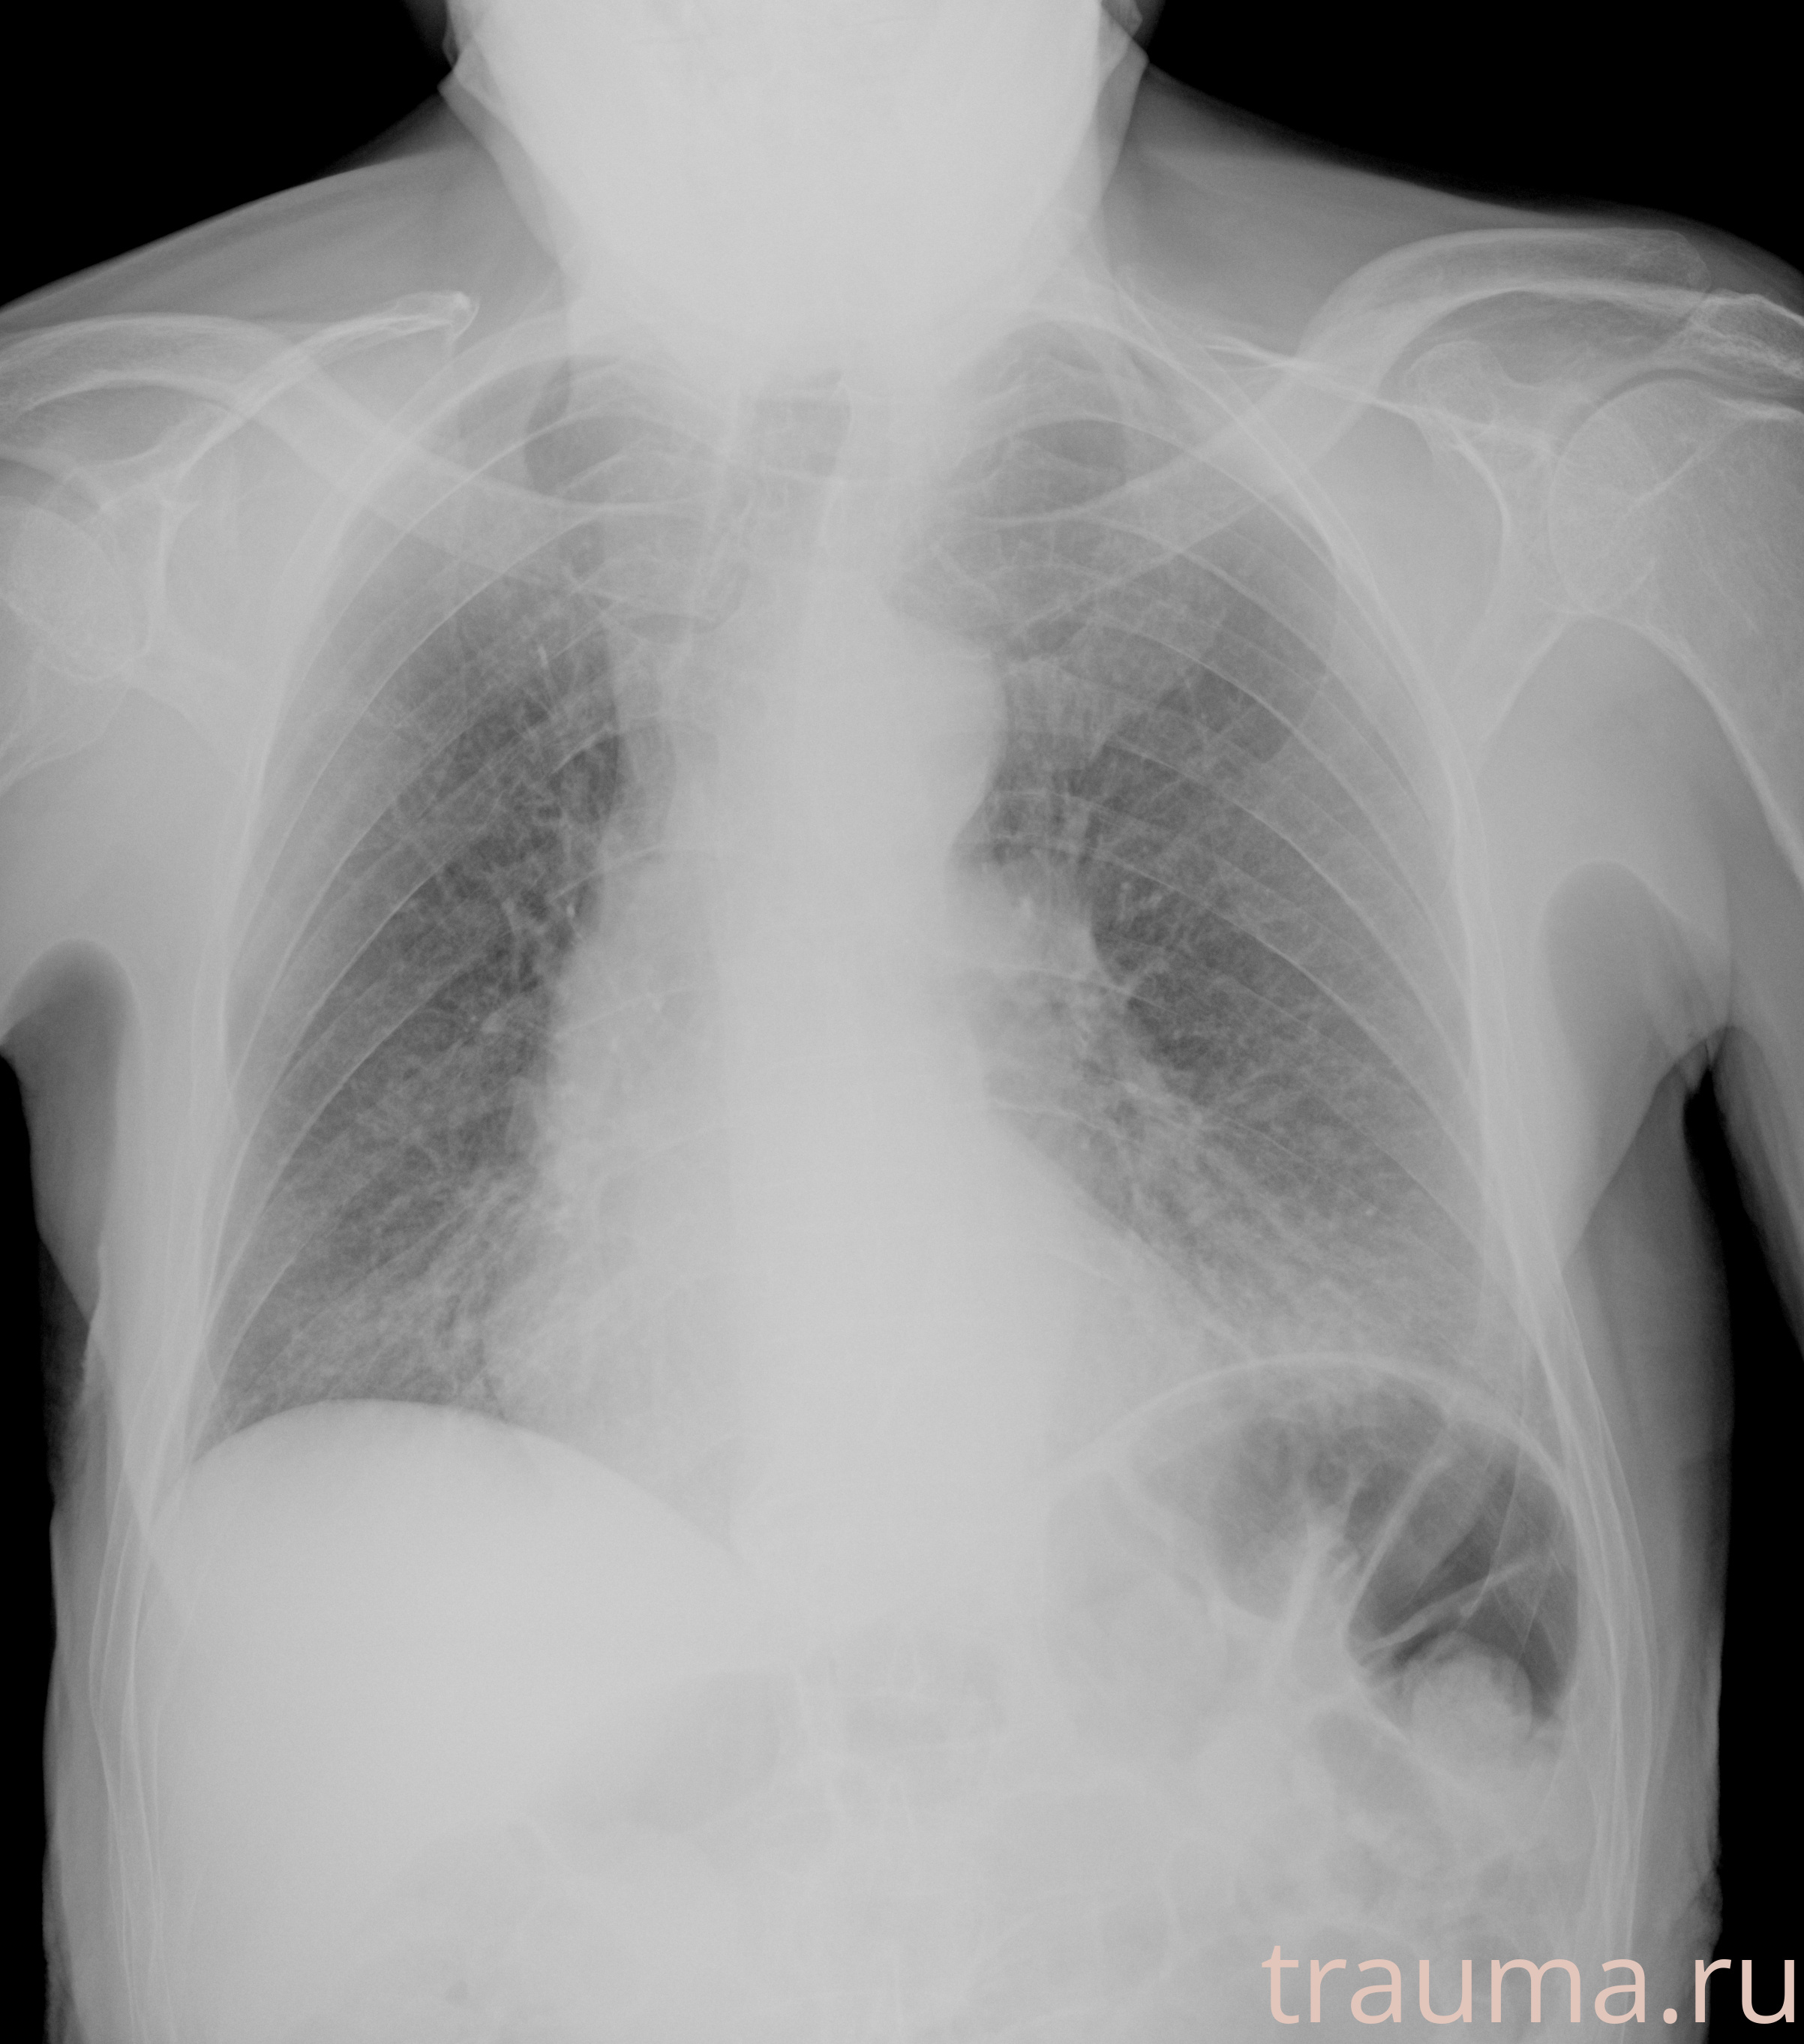

Рентгенограммы

Рентген на дому: по вашему адресу приезжает врач-рентгенолог, травматолог-ортопед с мобильным рентгеновским аппаратом, проводит диагностику травмы или заболевания, делает необходимые рентгенограммы, дает рекомендации по дальнейшему лечению. Получить качественные снимки в домашних условиях возможно благодаря уникальной методике, разработанной МосРентген Центром для института  Склифосовского